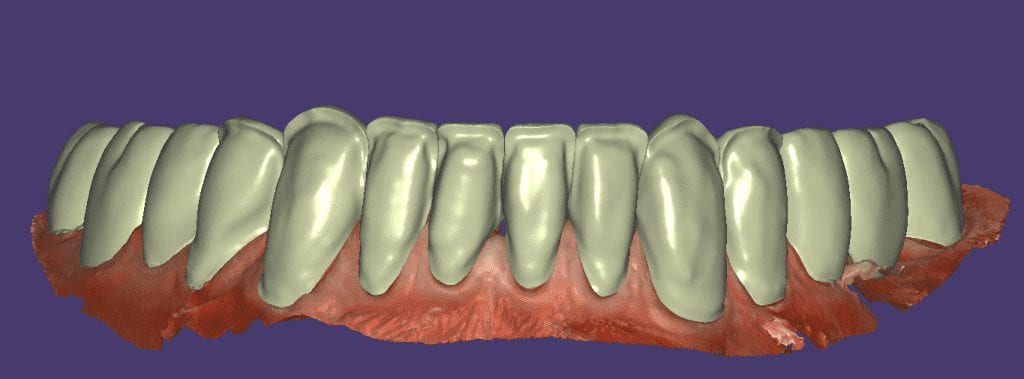

Over the course of a few appointments, the vertical dimension was reduced and the temporaries were adjusted to the patient’s desires. The new upper and lower arch were captured with the Medit i500 and the jaws were related to each other.

This was then imported into exocad where the prepped arches from a few weeks prior were force matched to the new bite

After the upper jaw was related to the temps, the same was done with the lower arch. Great care was taken to make sure the arches were properly related to each other throughout the process